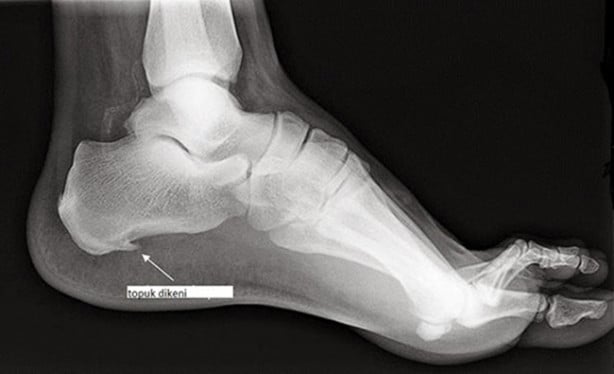

Topuk dikeni, aslında topuk kemiğinin alt kısmında diken benzeri çıntıya verilen bir isimdir.